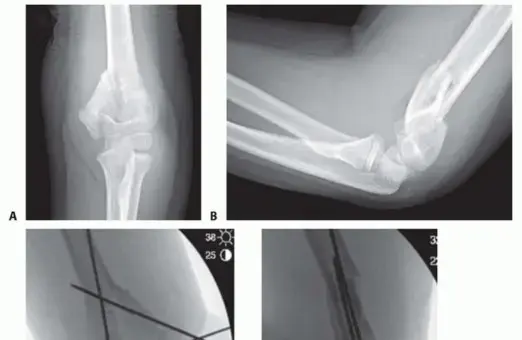

Open Reduction and Internal Fixation of Pediatric T-Condylar Fractures DEFINITION T-condylar fractures of the…